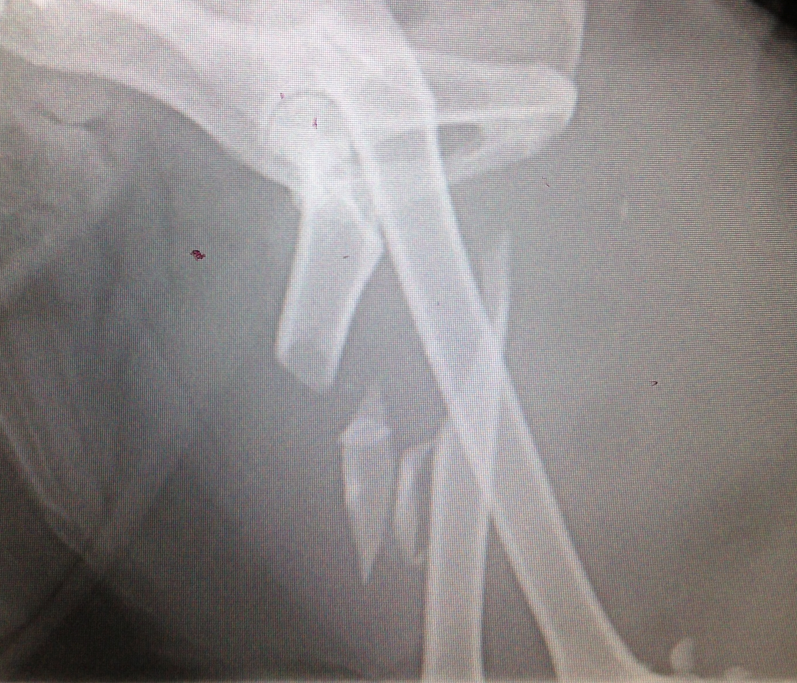

Geoffrey is a 7 year old Himalayan cross who went missing for 5 days, and when he eventually returned, had suffered a severe fracture to his femur in his left hind leg. The image below shows the severity of the break.

Geoffreys femur had shattered into several pieces

Geoffrey had suffered a comminuted fracture (a fracture where the bone has broken into several pieces) and had a lot of overriding (bone that has slipped out of its usual position) due to the break being 5 days old when he was presented to one of our hospitals. He was going to need surgery to repair it.